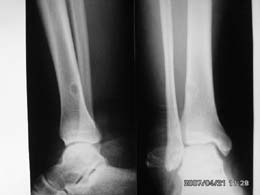

标题: CT7845:右胫骨下端,男,中学生打篮球时右踝扭伤 [打印本页]

标题: CT7845:右胫骨下端,男,中学生打篮球时右踝扭伤

男,中学生打篮球时右踝扭伤,拍片时发右胫骨下端楕圆形透亮影,是不是动脉瘤样骨囊肿,请讨论

胫骨后外侧见囊样低密度边缘硬化,其内见小点状高密度影,首先考虑骨样骨瘤

应该是比较典型的非骨化性纤维瘤:病灶偏于骨干的一侧,紧靠皮质下,呈类圆形,靠近髓腔侧有硬化边,病灶长轴平行于骨干,周围无骨膜反应和软组织肿块。与骨样骨瘤鉴别:后者具有明显或剧烈疼痛,“瘤巢”为其特征,在瘤巢周围有显著的反应性骨质增生。